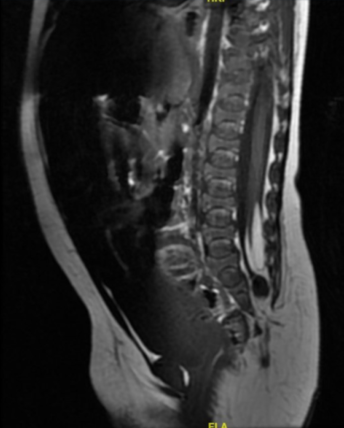

Durante su ingreso se realiza estudio ecográfico en el que se objetiva una masa grasa subcutánea en región glútea izquierda adyacente al pliegue interglúteo, que se continúa a través de un defecto de fusión de los elementos posteriores espinales con el saco tecal y el cono medular, que se muestra descendido (Figura 2). Estos hallazgos son compatibles con la presencia de un lipomielomeningocele y una médula anclada a la altura de L5, por lo que ampliamos el estudio con resonancia magnética (RM) (Figura 3) confirmando la presencia de un disrafismo espinal cerrado.

Figura 3: RM medular. Anclaje medular L5 con lipoma intradural L3-L5 rodeando al cono y dilatación quística distal al cono y al lipoma. Defectos de elementos posteriores sacrococcígeos